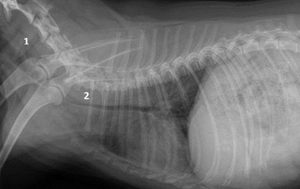

Методы диагностики

Так как клиническая симптоматика может развиваться в единичных случаях, а в основном слабо либо долгое время вовсе не показывать себя, то подтверждение диагноза «коллапс трахеи» всегда требует осуществления более тщательного осмотра с использованием нового оборудования.

Для начала стоит провести пальпацию трахеи собаки. Если болезнь всё-таки имеется, то форма трахеи очень сильно деформирована — на стенке в это время образуется жёлоб либо же сильное уплотнение.

Диагностика у животного может быть затруднённой. Держать питомца на одном месте и поймать время его вдоха-выдоха в большинстве случаев очень сложно. В некоторых случаях собака нуждается во введении успокоительного средства и бариевой кашицы, лишь таким способом она приходит в себя и становится спокойнее. Иногда осуществляют забор ткани трахеи для определения возбудителя болезни и анализа крови на чувствительность к препаратам-антибиотикам.

Время от времени стоит привозить собаку в ветеринарную клинику на эндоскопию и рентгенологическое обследование, чтобы внимательно следить за имплантом или стентом.

Диагностика коллапса трахеи обычно включает физический осмотр ветеринаром, прослушивание дыхательных звуков и рентгенографию грудной клетки. В некоторых случаях может потребоваться бронхоскопия для визуализации трахеи и оценки степени коллапса.